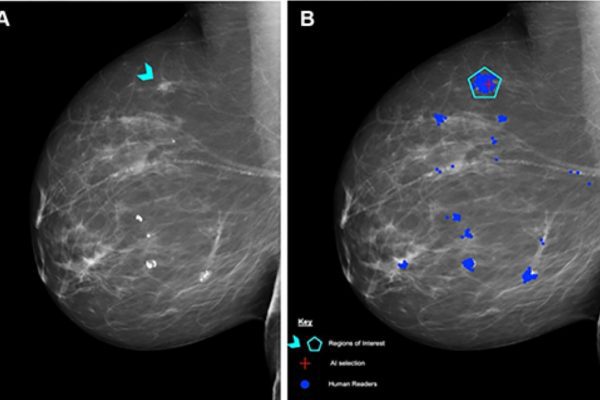

La IA mejora la detección del cáncer de mama sin aumentar los falsos negativos

El ensayo MASAI, uno de los más grandes realizados hasta ahora, mostró que el uso de inteligencia artificial en el cribado mamográfico mantiene la seguridad clínica, mejora la sensibilidad y reduce la carga de trabajo de los radiólogos. Los resultados abren la puerta a su adopción a gran escala en los sistemas de salud. La…